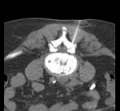

Under computer tomographic or magnetic resonance imaging control, drugs are injected with millimeter precision into the neuralgic points of the spine using fine injection needles. In many patients, this can result in significant pain relief or even freedom from pain. All pain therapy treatments can be carried out on an outpatient basis without any problems due to the low complication rates. A treatment takes a maximum of 10 to 30 minutes.

FacettenblockadeFacet block is a minimally invasive therapeutic procedure for diffuse, motion-dependent non-radicular (not caused by the nerve root) back pain. These complaints are due to wear and tear of the small vertebral joints, caused by wear and tear, poor posture or bending of the spine. These degenerative changes in the small vertebral joints cause approximately 90% of all back pain conditions.